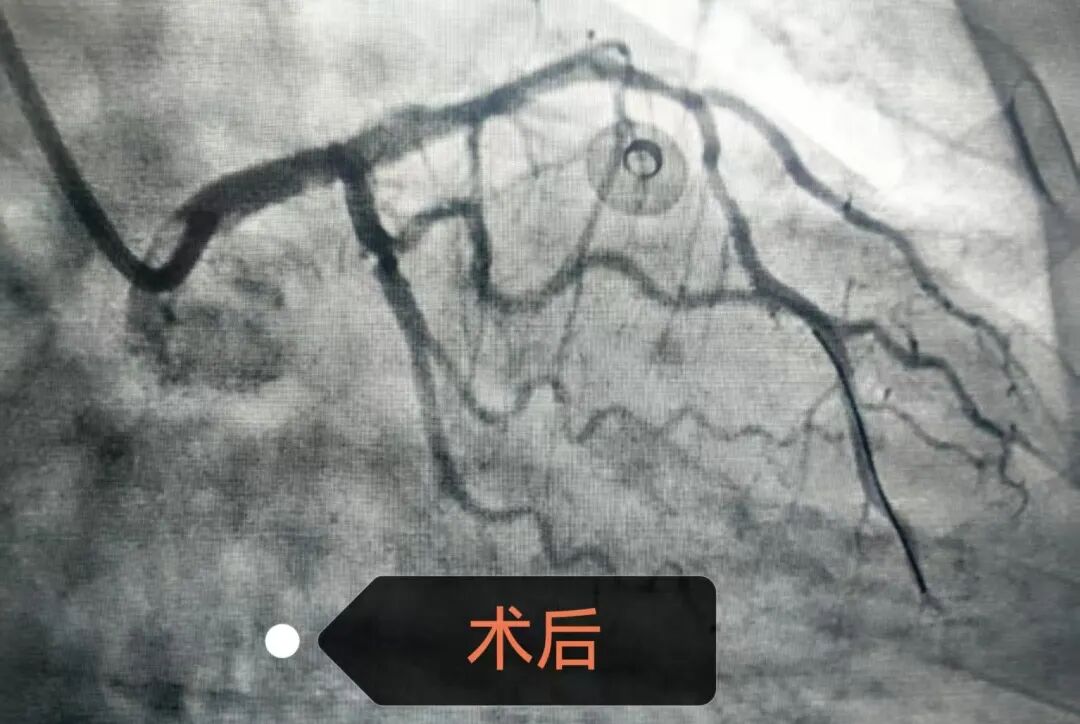

术中,团队凭借丰富的经验,快速完成指引导管深插,获得稳定支撑。在导丝通过闭塞段后,果断使用球囊扩张,迅速重建前向血流。随后,精准植入药物洗脱支架,完美覆盖病变,实现血管的充分开通与血运重建。

整个过程节奏紧凑、操作流畅,患者术中生命体征全程平稳。术后患者恢复良好,心功能明显改善,目前患者已平安出院半月,随访状况稳定。